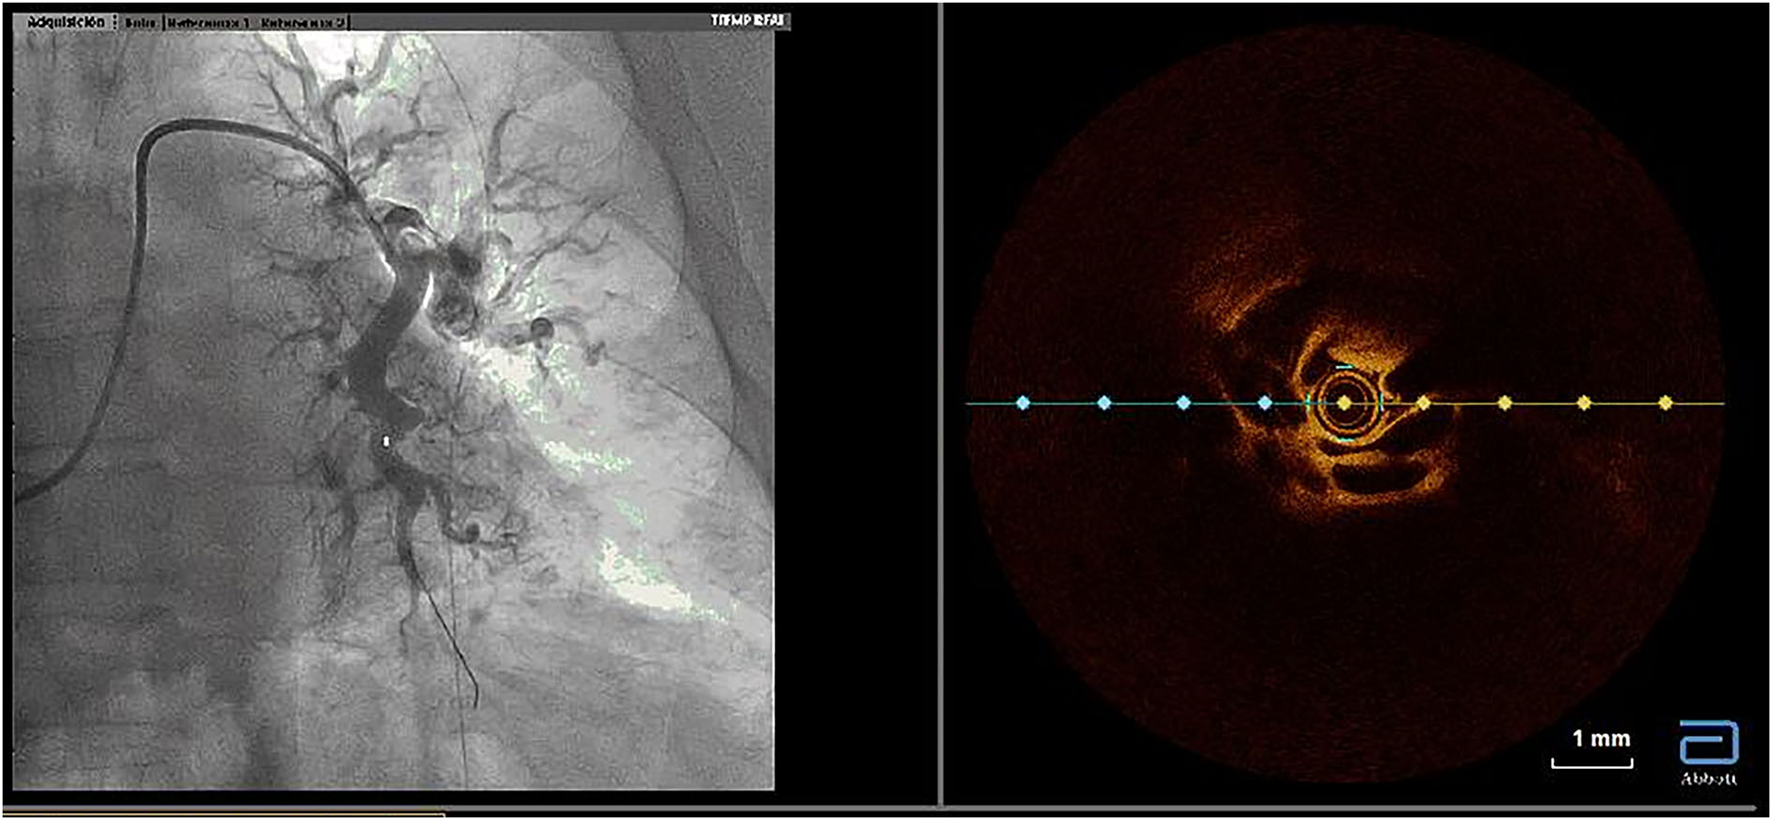

Figure 3

Utility of optical coherence tomography to confirm CTEPH organized thrombi inside pulmonary arteries. Organized thrombi inside the superior segmental branch of the left lower lobe. CTEPH, chronic thromboembolic pulmonary hypertension.